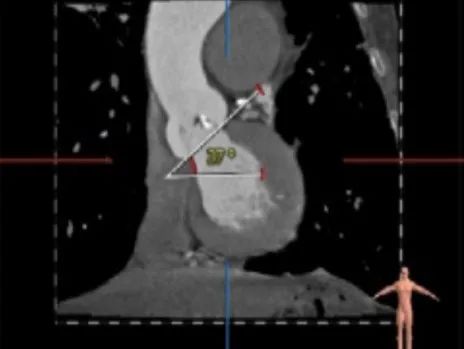

主动脉根部测量:

ANNULUS

SOV DIAMETER

LVOT

STJ

ASCENDING AORTA

LEFT VENTRICLE